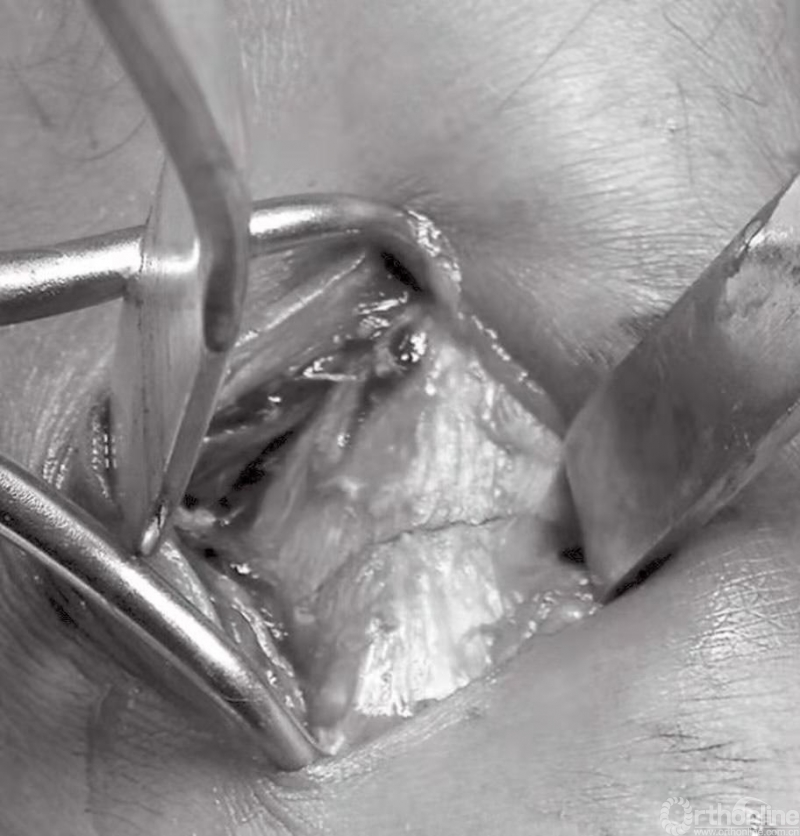

为使用复位钳,需在骨折线上方钻一个小孔(图13)。用持钩或较小的复位钳复位内踝(图14)。将一个尖端置于胫骨远端中的小孔,另一个尖端则放在骨折片尖部。要避免压碎骨折片,在治疗老年患者时尤其注意。为防止骨折片复位不良或发生旋转,应在骨折线的前缘和外侧面检查复位的情况。

图13 为使用复位钳,需在骨折线上方钻一个小孔

图14 持钩或较小的复位钳复位内踝